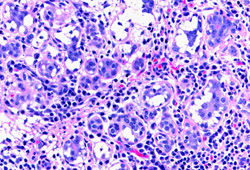

Lactational mastitis: microscopy image showing hyper-secretory glands associated with inflammation

From the collection of Liron Pantanowitz, MD, Tufts University School of Medicine, MA